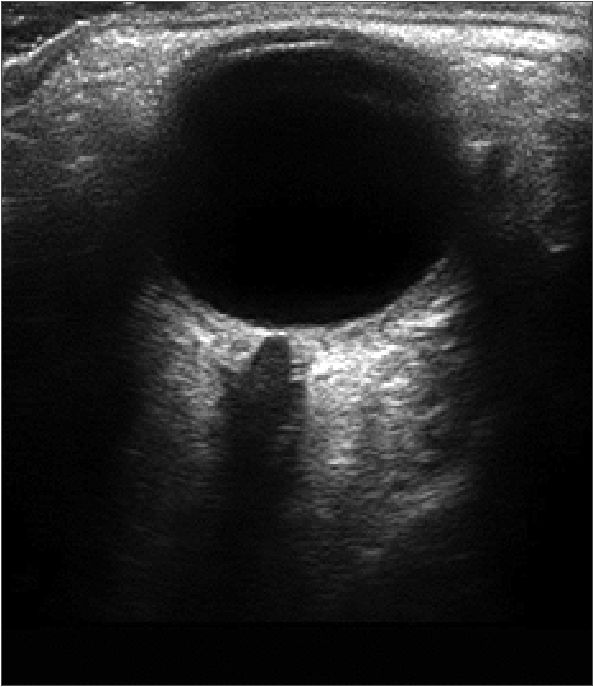

Dicha medición se realizó tanto en el plano sagital como en el axial del globo ocular; de ellas, se determino la mejor imagen, la cual fue definida como aquella con una visualización adecuada de la entrada del nervio óptico al globo ocular, los límites de la VNO y el nervio óptico. Esta se congeló, y se midió el DVNO 3 mm detrás del globo ocular a lo largo del eje perpendicular al disco óptico (Figuras 1 y 2).

Figura 1. Entrada del nervio óptico al globo ocular, los límites de la VNO y el nervio óptico.